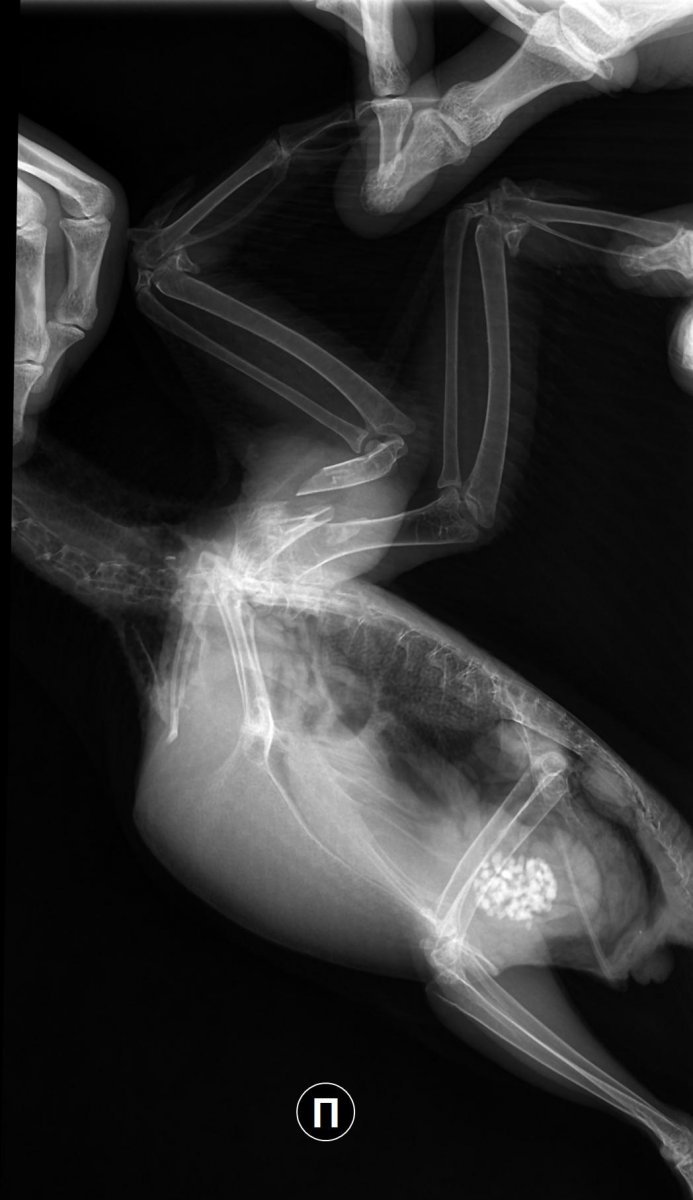

Рентген №1 - 08.121_3011977922r.thumb.jpg.1c03db7fd202f6f6e764bf55e9a4103d.jpg

1_3011977922r.thumb.jpg.1c03db7fd202f6f6e764bf55e9a4103d.jpg1_3011993622r.thumb.jpg.7575556377acddc5708415dfcdcf6558.jpg

Рентген контрольный - 22.12

1_3131795322r.thumb.jpg.d84909cef2a8ef1a6f8861285e32d1be.jpg1_3131813522r.thumb.jpg.2b83701bfbf4fd71082afc4022d192bd.jpg

Врач после второго рентгена говорила, что надежда ещё не потеряна, но скорее нет чем да, а если полетит, то не раньше чем через месяц. Прошло уже два, прогресс крайне мал (

Если представленные снимки свежие- то летать он не будет, т.к. за 3 месяца после аварии у него нет даже признаков консолидации или хотя бы образования ложного сустава.

на представленных снимках перелом полный , с чрезвычайно большим смещением всех отломков.  Если не производилась хоть какая-то репозиция отломков, то там нечему и некуда прирастать... там расстояние между частями отломков долее 5 мм, а то и все 8.

Снимки датированы - 08.12.22; 22.12.22